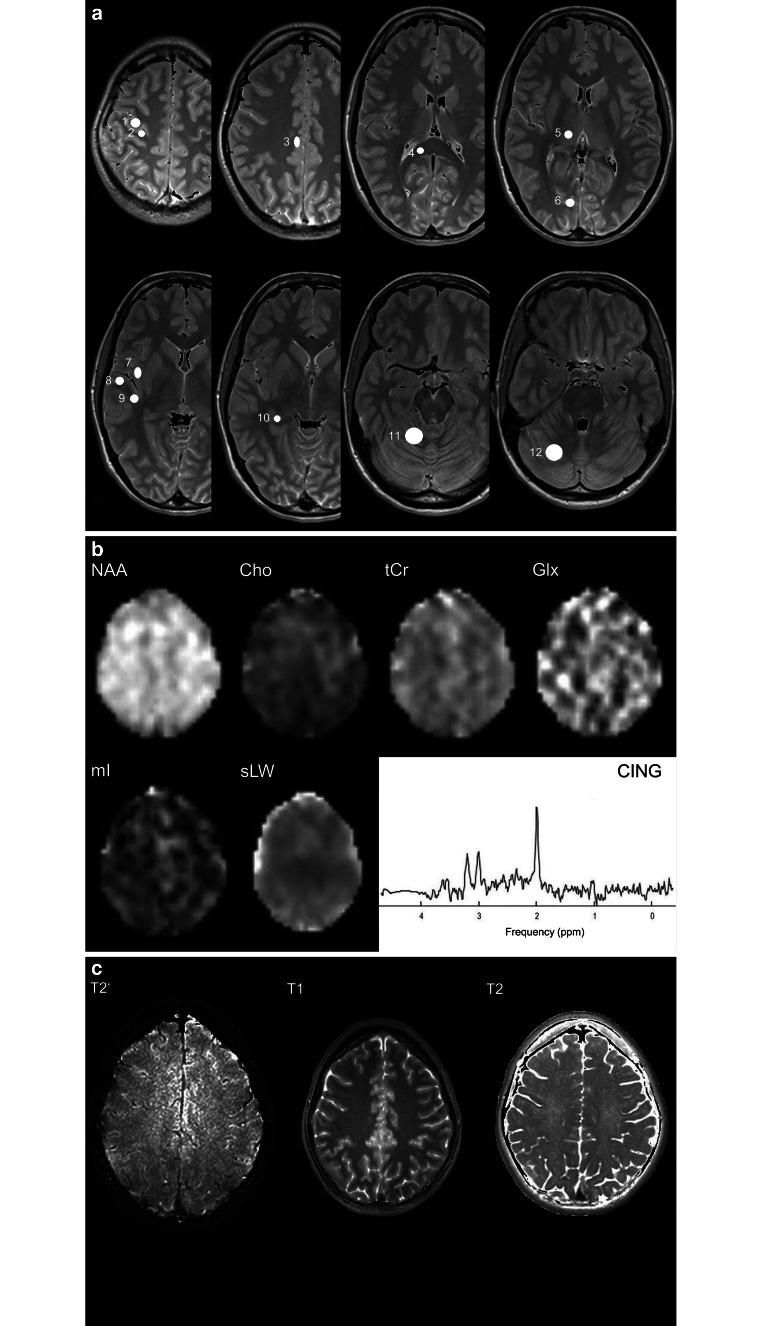

In this study, 60 healthy participants with evenly distributed ages (between 21 and 69 years) and sex underwent MRI examinations at 3T including whole-brain H‑MRSI. The concentrations of the metabolites N‑acetylaspartate (NAA), choline-containing compounds (Cho), total creatine and phosphocreatine (tCr), glutamine and glutamate (Glx), and myo-inositol (mI), as well as the brain relaxation times T2, T2' and T1 were measured in 12 regions of interest (ROI) in each hemisphere. Correlations between measured parameters and age were estimated with linear regression analysis and Pearson's correlation test.

Significant age-related changes of brain regional metabolite concentrations and tissue relaxation times were found: NAA decreased in eight of twelve ROIs, Cho increased in three ROIs, tCr in four ROIs, and mI in three ROIs. Glx displayed a significant decrease in one ROI and an increase in another ROI. T1 increased in four ROIs and T2 in one ROI, while T2' decreased in two ROIs. A negative correlation of tCr concentrations with T2' relaxation time was found in one ROI as well as the positive correlations of age-related T1 relaxation time with concentrations of tCr, mI, Glx and Cho in another ROI.